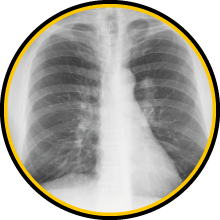

You must have silicosis before you can get lung cancer from silica dust